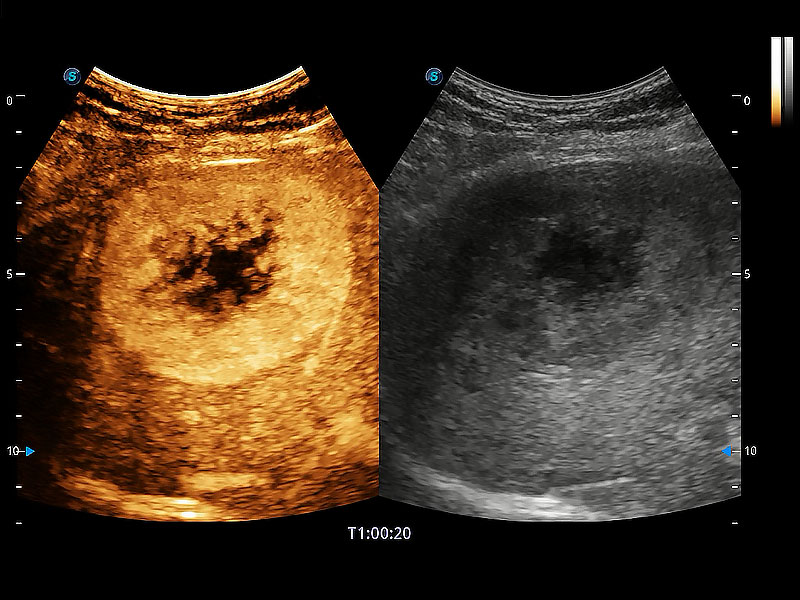

(犬)四腔心MQA

(犬)二腔心血流